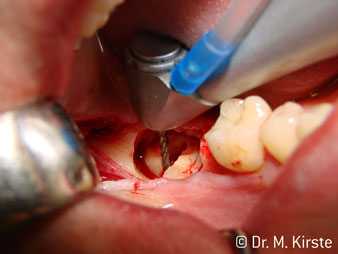

The 45° angle of the handpiece has been specially selected for its wide range of advantages. Colleagues who work in surgery, and for whom this handpiece was primarily developed, will soon appreciate the ability to work efficiently in very restricted spaces. In wisdom tooth extractions in particular (fig. 2) there is no need for large-scale spreading of the soft tissues in the cheek region (fig. 3). The design of the handpiece head combined with turning the head slightly during preparation allows work to be carried out quickly and safely in the retromolar region.

The professional design of the bearings inside the handpiece head guarantees quiet running of the bur; this makes for an impressively atraumatic cut in the separation of tooth and root (fig. 4-9).